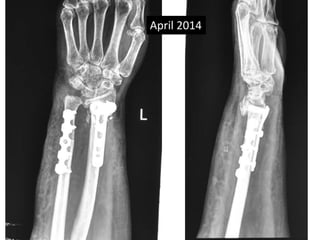

Surgery

• Volar exposure

• Removal of scar tissue and clearing of bone

ends.

• Release of soft tissue contractures.

• Shortening of ulna and plating.

• Plating of radius with bone grafting.

Feb 2013

April 2014

Sept 2013